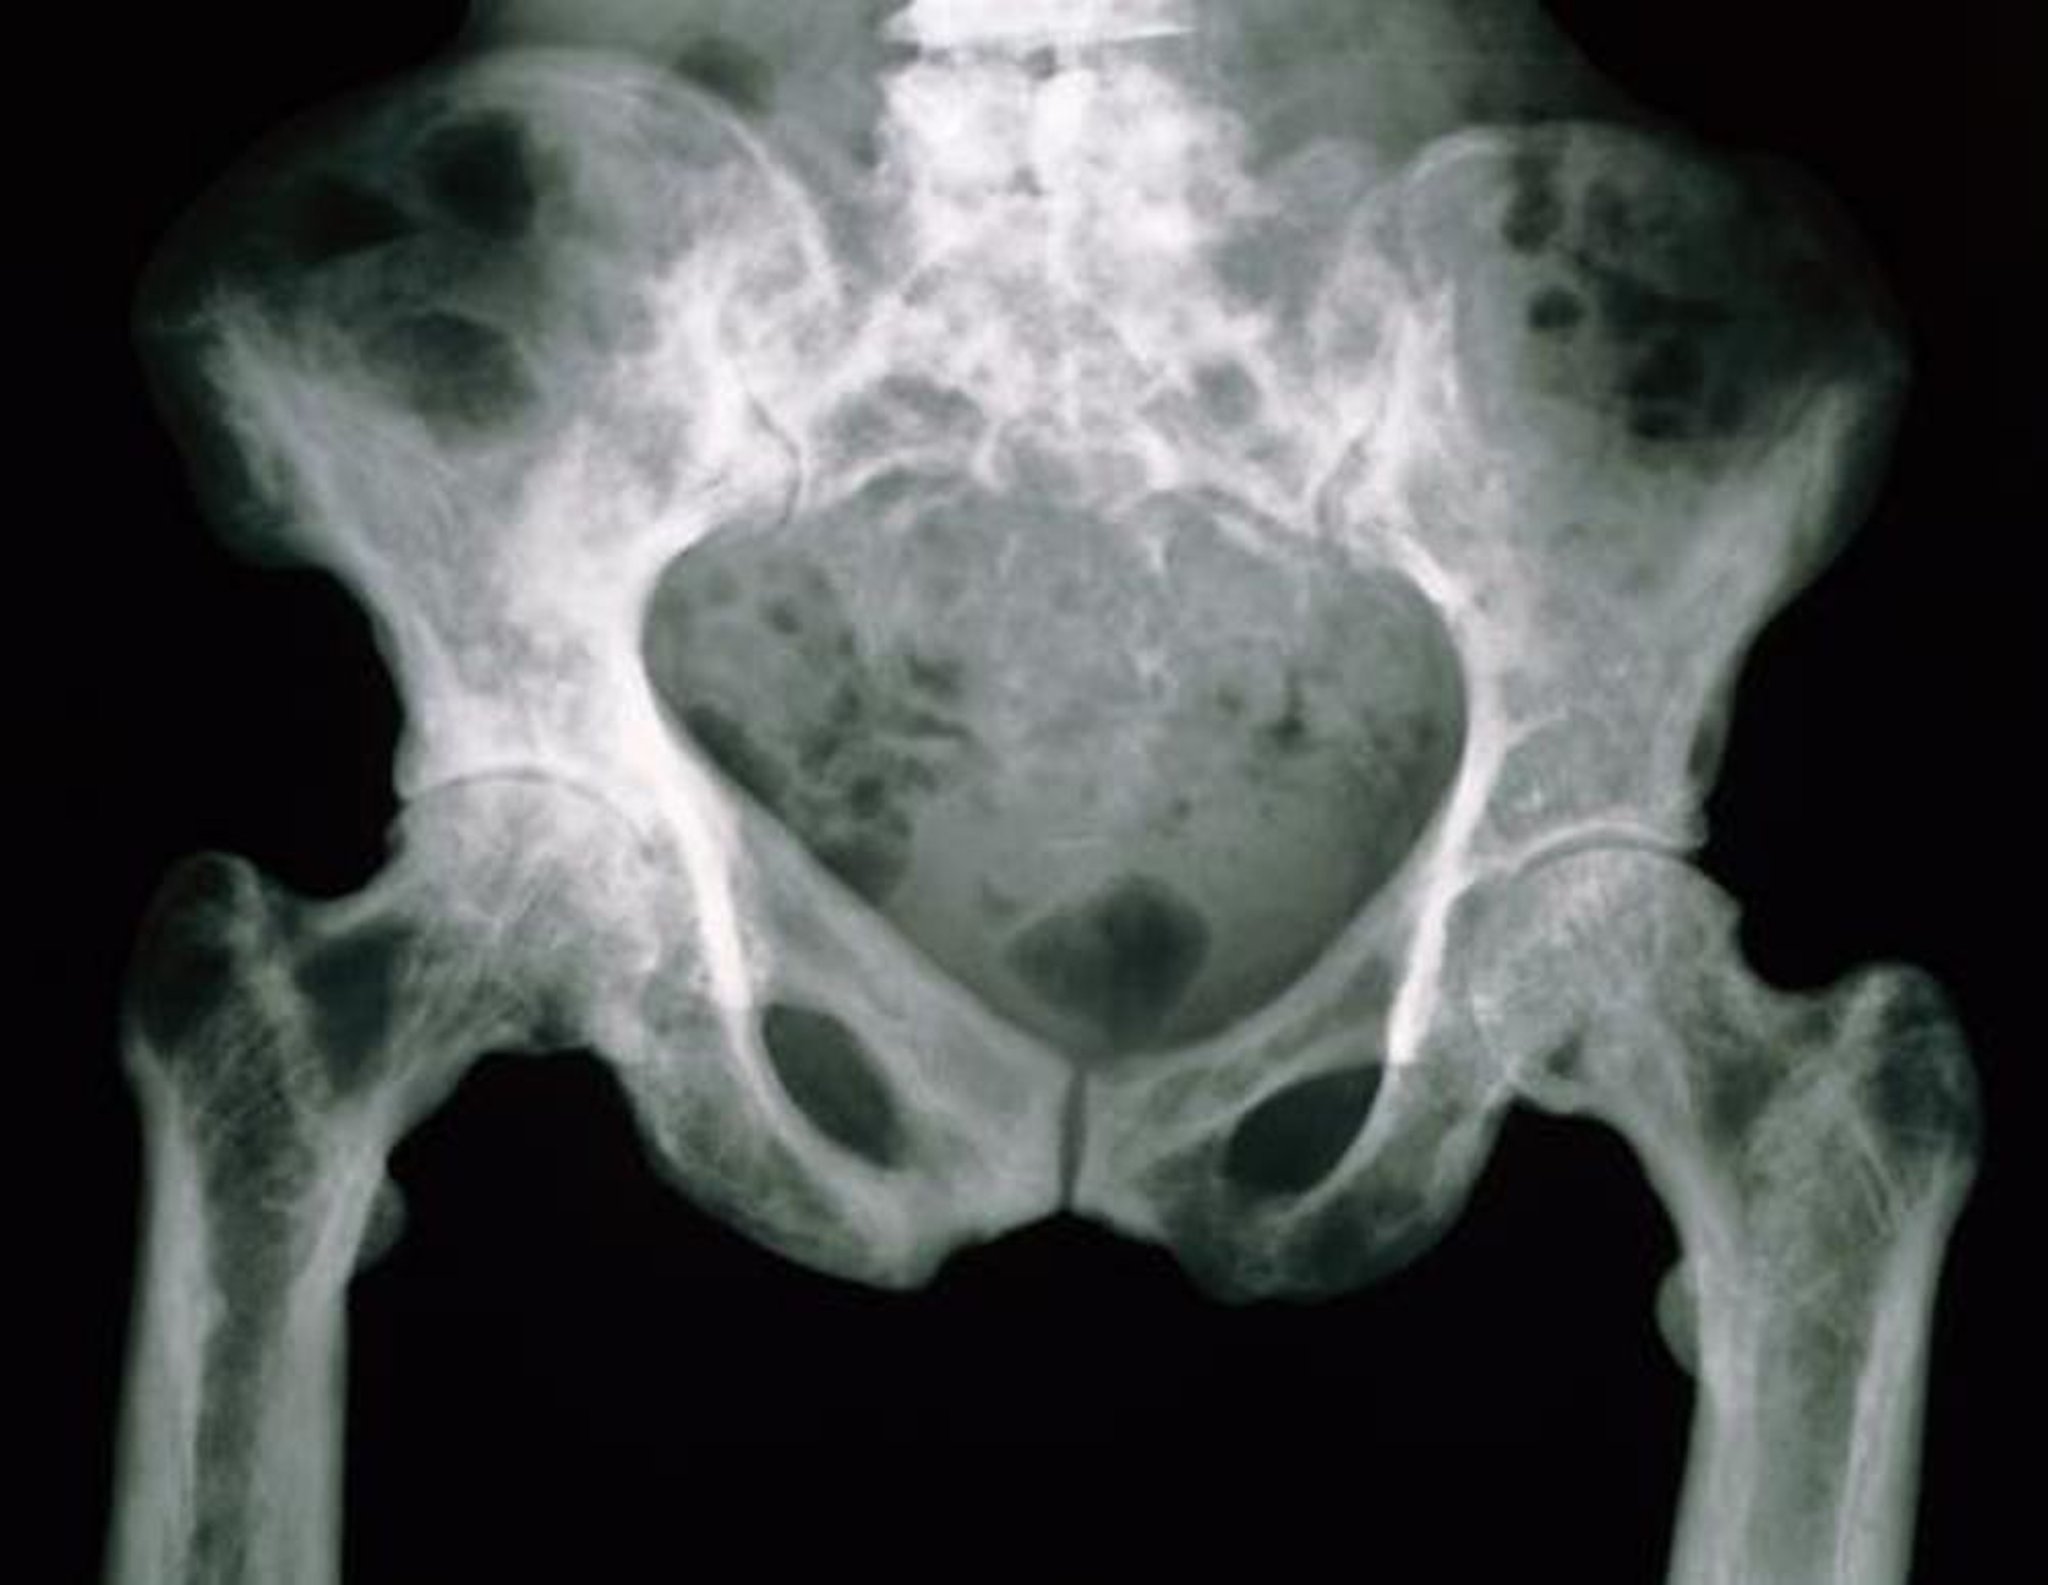

Рентгенограмма таза при болезни Педжета

На данном рентгеновском снимке тазовые кости выглядят мраморными из-за их повышенной пористости.